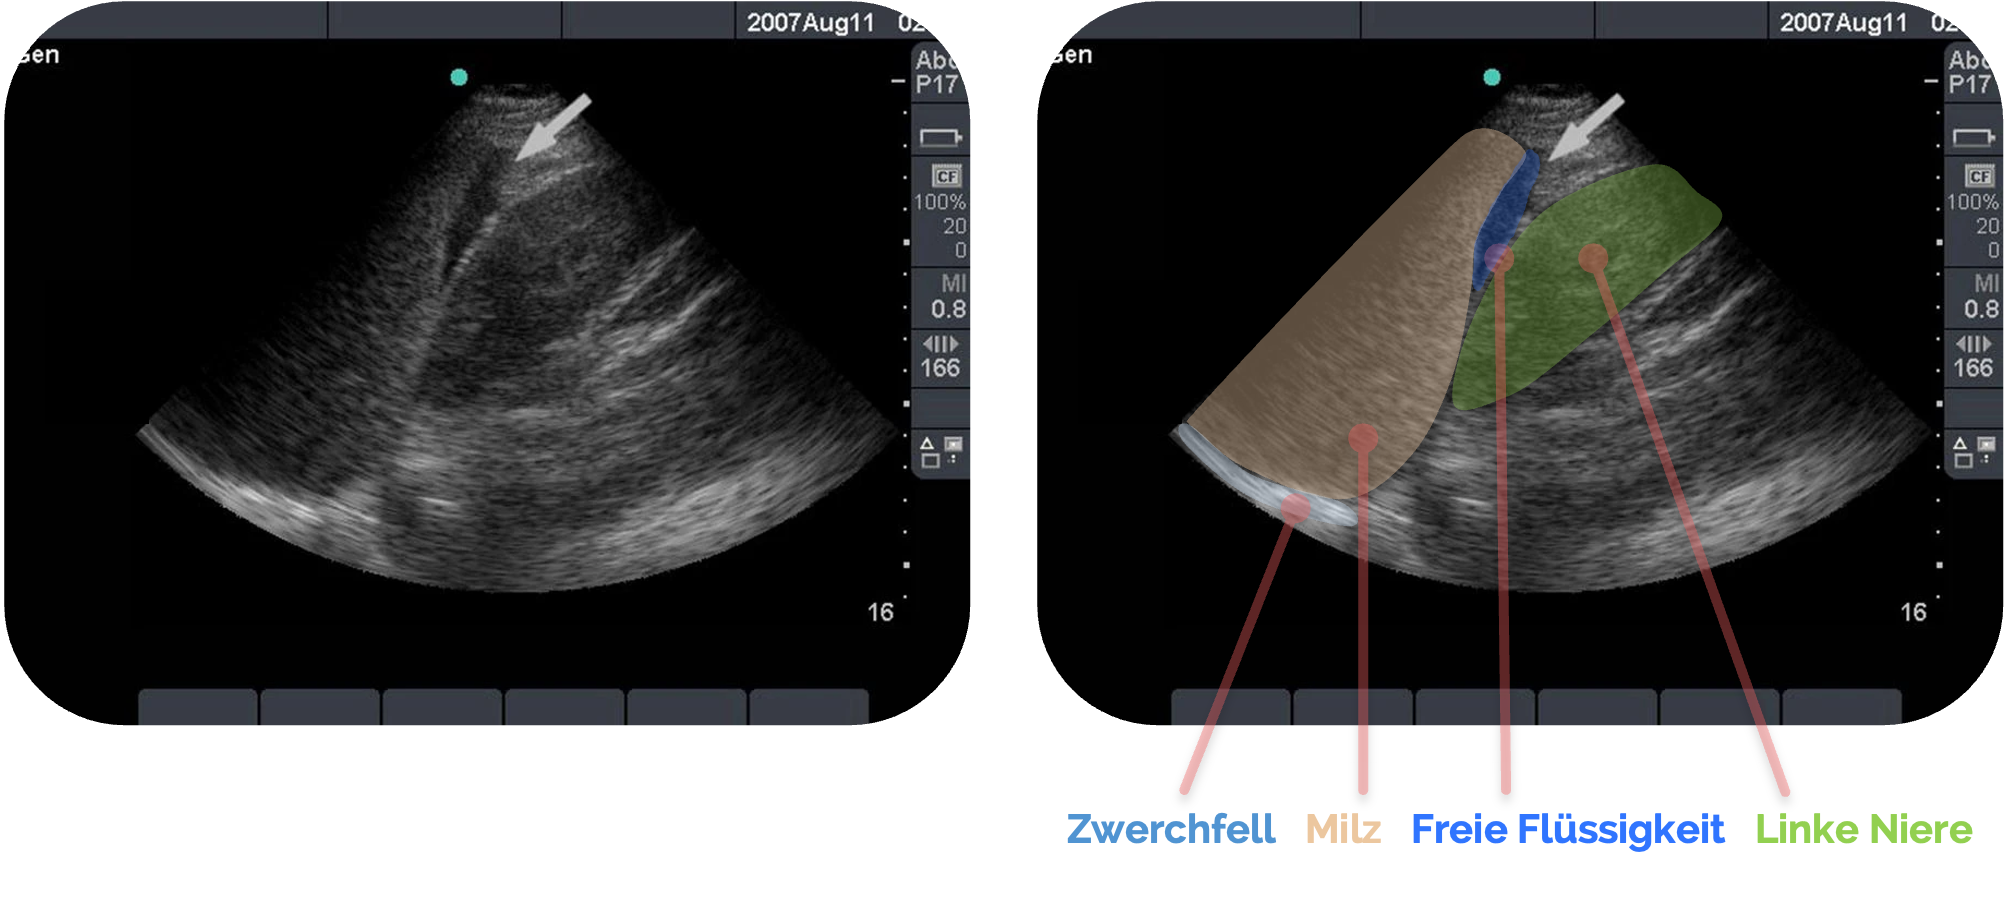

Freie Flüssigkeit im Koller-Pouch

Freie Flüssigkeit zeigt sich sonographisch als echofreier oder echoarmer Spalt zwischen Milz und linker Niere, häufig in Form einer sichelförmigen Zone, die der Schwerkraft folgend an der tiefsten Stelle des Recessus splenorenalis liegt.

Bereits kleine Flüssigkeitsmengen werden in diesem Bereich früh sichtbar, da der Koller-Pouch anatomisch eng begrenzt ist, insbesondere bei Milzrupturen, kann sich hier Flüssigkeit sammeln. Mit zunehmender Flüssigkeitsmenge kann sich der Spalt vergrößern und nach kranial oder kaudal ausdehnen.

Eine sorgfältige Beurteilung in mehreren Ebenen ist entscheidend, um Artefakte von echter Flüssigkeit zu unterscheiden und die Ausdehnung der Ansammlung zuverlässig einzuschätzen.

Freie Flüssigkeit sammelt sich insbesondere im subphrenischen Raum und entlang der lateralen Milzoberfläche. Diese Bereiche, häufig nicht nur im eigentlichen Koller-Pouch, sondern auch um die Milz herum, sollten daher stets mituntersucht werden, da Flüssigkeit dort durch die anatomische Verbindung der Rezessusräume leicht übertreten kann.

Figure 8 aus Ketelaars, R., Reijnders, G., van Geffen, GJ. et al. ABCDE of prehospital ultrasonography: a narrative review. Crit Ultrasound J 10, 17 (2018). https://doi.org/10.1186/s13089-018-0099-y. Es wurden die Markierungen und Beschriftungen ergänzt.

Während freie Flüssigkeit typischerweise den Raum zwischen Milz und Niere füllt, bleibt beim subkapsulären Hämatom die Milzkontur nach außen glatt, aber nach innen deformiert.

Ein intraparenchymatöses Hämatom zeigt dagegen eine umschriebene echogene Strukturveränderung ohne klare Flüssigkeitssichel. Entscheidend ist der Verlauf der Milzkapsel: Ist sie durchbrochen oder vorgewölbt, besteht Verdacht auf eine Ruptur.